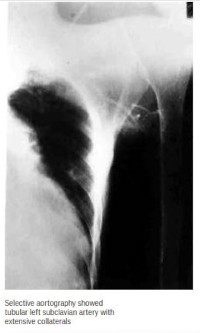

Takayasu arteritis (TA) is a chronic vasculitis of unknown aetiology involving the aorta and its major branches. It could also involve the coronary and pulmonary arteries. It was first noted in 1908 by a Japanase ophthalmologist, Mikijo Takayasu, who described the case of a 21 year old woman whose optic fundi 1 exhibited peculiar anastomosis. The disease has a worldwide distribution, but it is more common in South East Asia. It affects mainly young women, who account for about 90% of all cases in a 2 series from Japan. An international survey by Nunearo et al showed that the female to male ratio decreases as one 3 moves from east to west. On the African 4, 5 scene, few cases have been reported. The cases that have been reported from 6 South-West Nigeria were all females. We hereby report a case of TA in an adult Nigerian from the North. This to the best of our knowledge is the first case reported in a Nigerian male in literature.